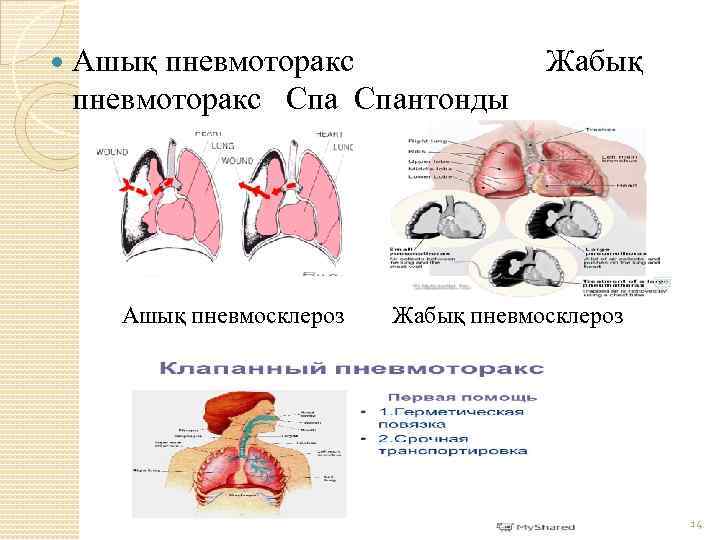

Схемы дыхания: Пневмоторакс на изображениях